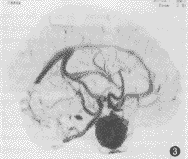

脑血管成像示:(1)55例CTA均可清楚显示1~4级脑血管结构、Willis环和大脑前、中、后动脉主干及其分支情况。(2)脑动静脉畸形12例,其中枕叶3例,颞叶5例,额叶3例,顶叶1例。可见异常增粗迂曲的血管,9例血管呈团状,5例可见增粗的引流血管,5例部分血管有钙化,均可清楚地观察到畸形血管的位置和范围(图1)。(3)动脉瘤2例,清楚地观察到瘤体大小、位置、形态,以及与血管的关系(图2,3)。(4)脑肿瘤19例,其中9例脑膜瘤可见肿瘤邻近血管被推移或包裹,4例可见肿瘤表面有异常血管(图4)。4例胶质瘤和4例转移瘤可见瘤体呈不均匀强化,或不强化,周围有不同程度水肿,肿瘤附近血管被推移(图5);位于第4脑室的室管膜瘤和位于中颅窝蝶骨翼旁的三叉神经瘤可见瘤体呈不同程度强化,室管膜瘤有血管推移。(5)大脑中动脉及分支栓塞3例,2例大脑中动脉主干变窄、变细,远侧方血管变细、变少(图6);1例大脑中动脉顶后分支变细,变窄,远侧方血管较少;(6)脑挫裂伤及脑脓肿可见局部血管有不同程度推移,脑积水以两侧大脑前、中动脉抬高较为明显。

图3 同上,矢状面可见动脉瘤瘤蒂